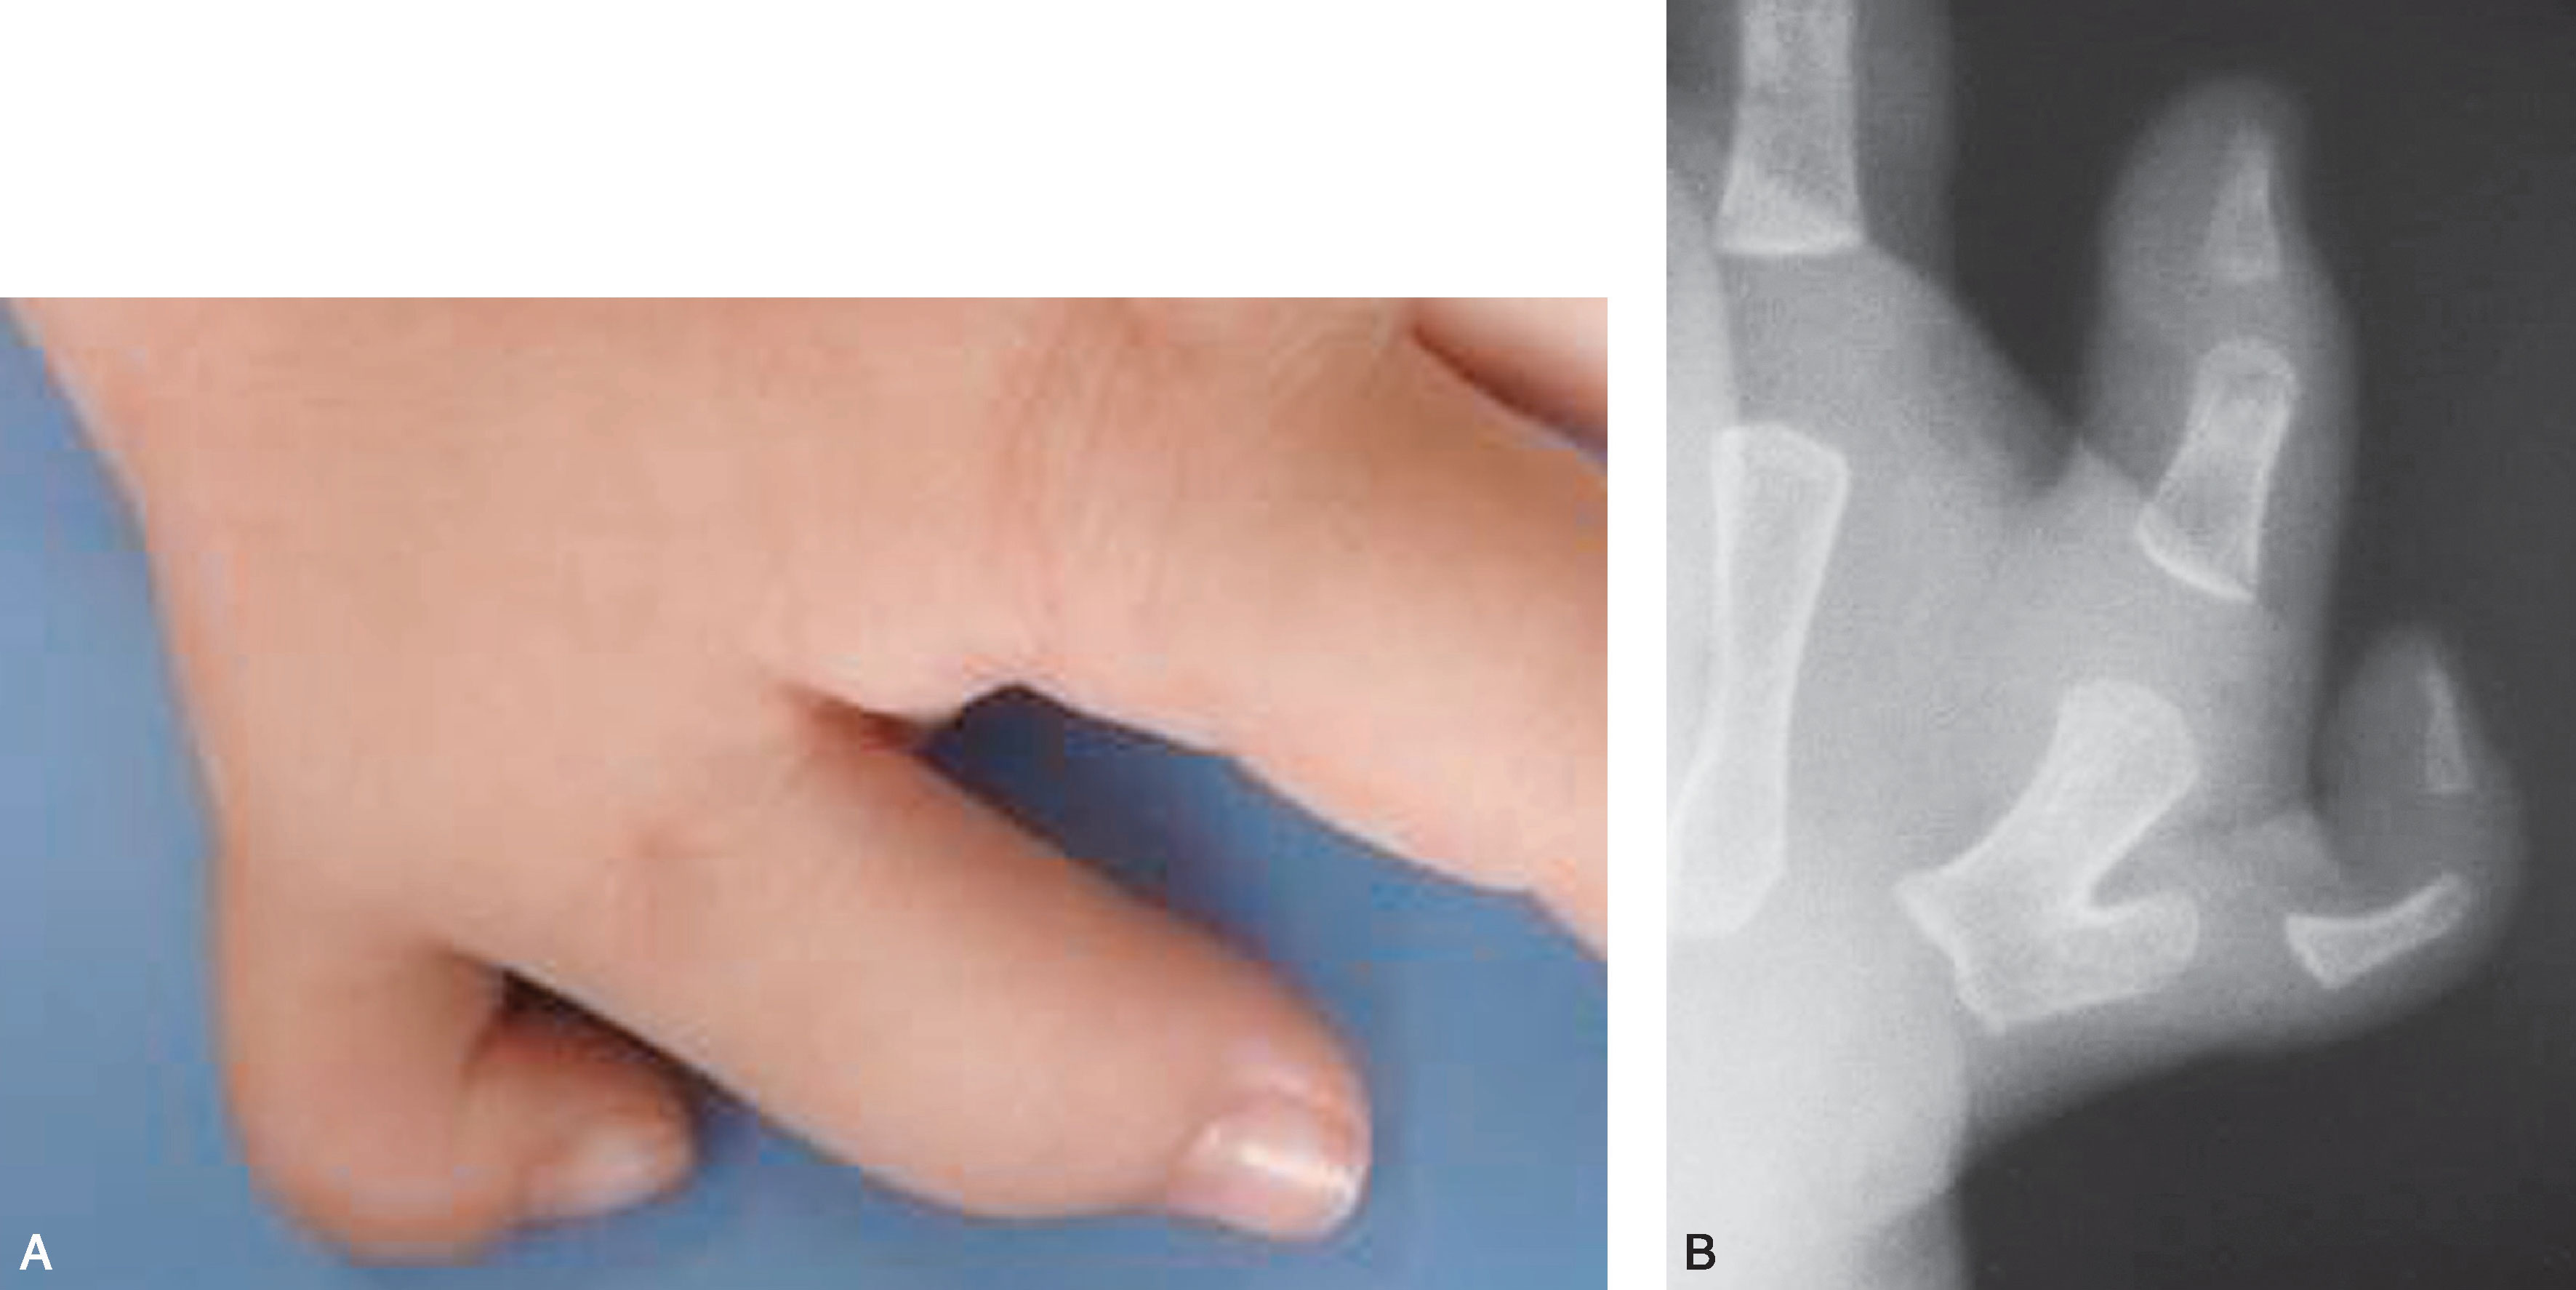

2.Ⅱ型 远节指骨完全分开,两个骨骺,近节指骨增宽,远端有两个关节面与近节指骨形成两个关节(图2-1-5~图2-1-11)。

图2-1-12 Ⅲ型病例1

A.主、次拇指外形及大小接近,可以选择主、次拇指融合术式;B.X 线片显示桡侧末节指骨较小,其近端可见一个细小骨,与尺侧远节指骨难以融合为一个规整的指骨,尺侧拇指骨关节形态及力线均可,因此切除桡侧拇指保留尺侧拇指更合理